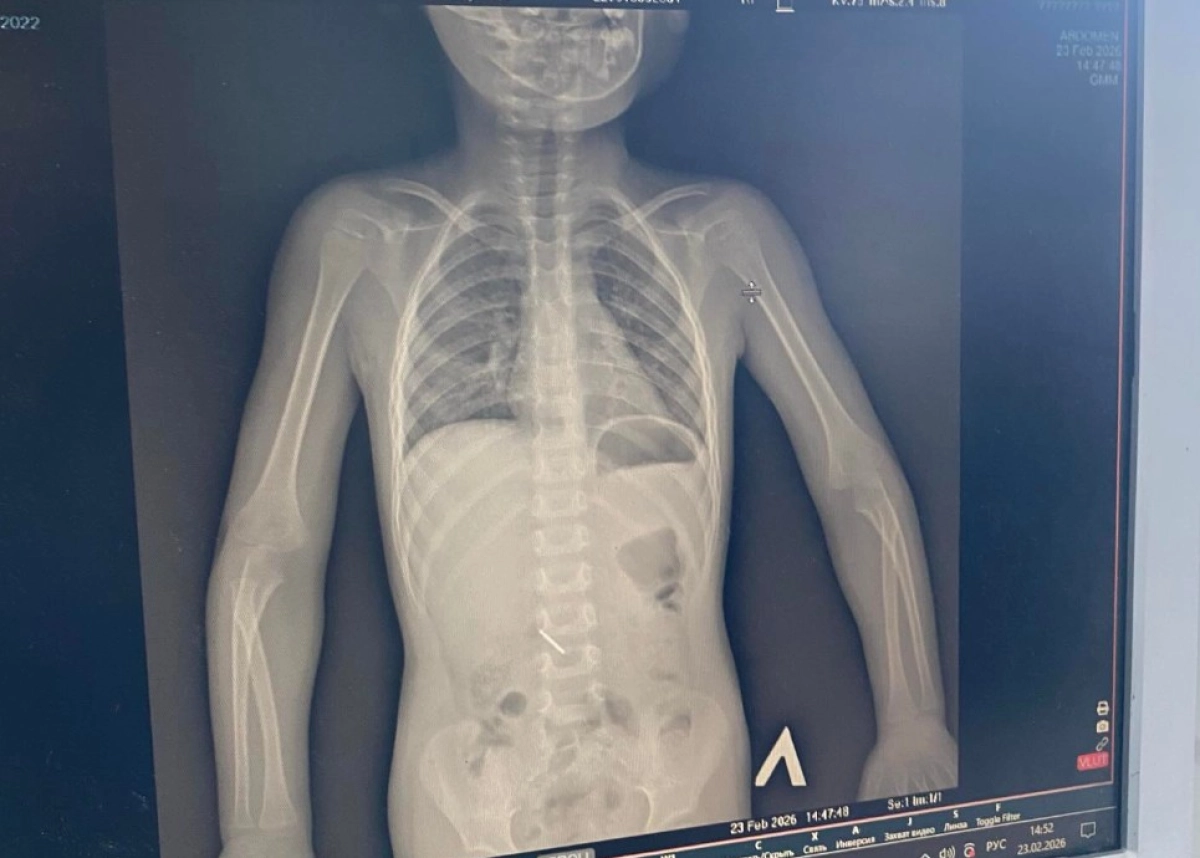

Родители не стали ждать и самостоятельно обратились в многопрофильную областную детскую больницу. За несколько дней ребенку провели два рентгенологических исследования, осмотр хирурга и процедуру ФГДС (фиброгастродуоденоскопию). На 26 февраля, как сообщает мать, инородный предмет еще не вышел естественным путем.